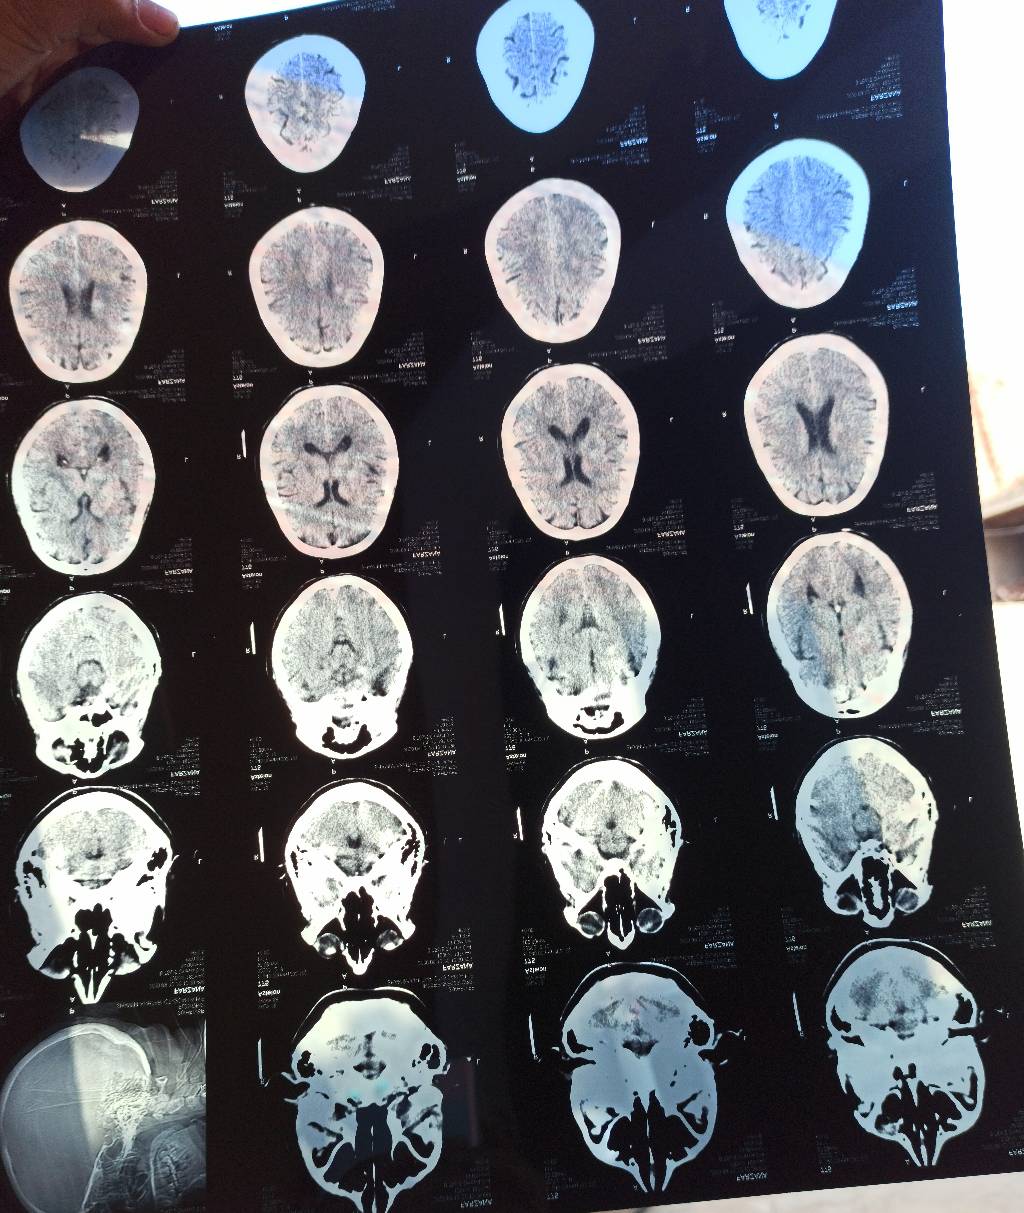

Hi there! Actually last Saturday my mother has paralyzed attck as her bp shoot to 180 as well as her suger is upto 350+. We quickly rush her to allied hospital fsd, they treated well and by Allah almighty she's fine Alhumdullilah. Rather than of it i have consulted with dr jibran via marhan and he suggested some best medicines. My mother is recovering now. But now my question is that im going to upload ct scan and asking for doctor advice as is it fine, i mean paralyzed attck isn't attack my mother brain? What type of precautions we have to take so that next time its can't happen. JazakAllah

Attach Photo here: